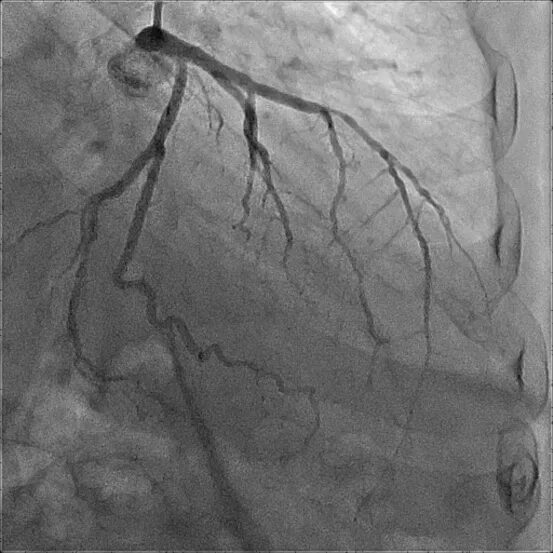

Атеросклероз левой коронарной артерии